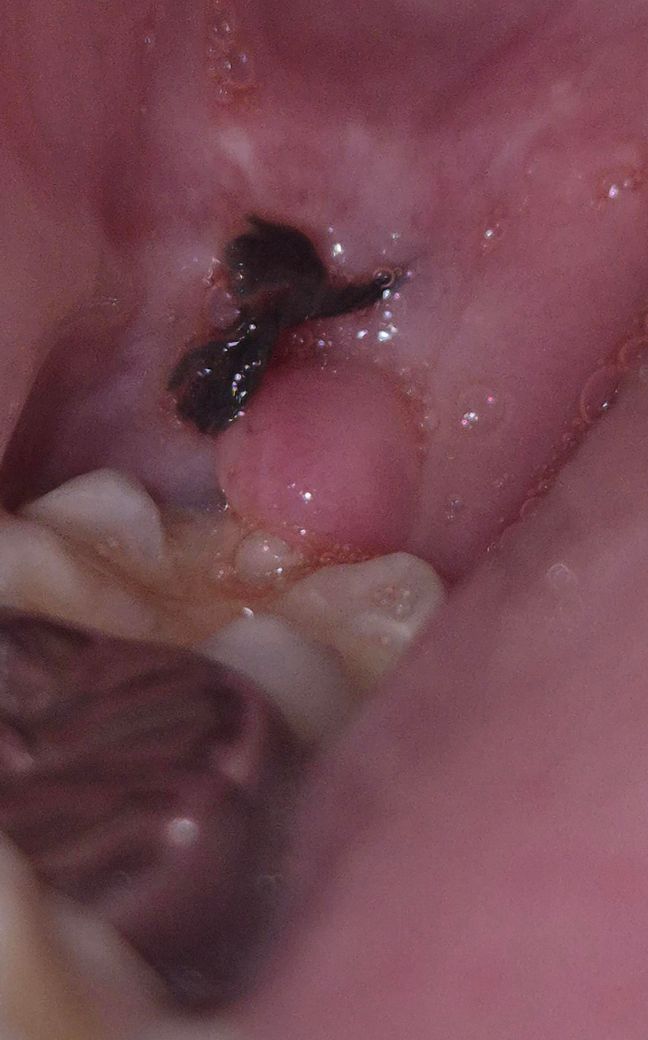

통증은 없는데 7일차에도 피가 조금씩은 나오는데 정상인가요?

사진처럼 저렇게 약간 볼록하게 회복되는게 정상인가요?

사랑니 발치 후 일주일까지 미세한 출혈은 상관 없습니다. 볼록한 것은 시간이 지나면 없어질겁니다.

실밥으로 봉합을 해서 잇몸이 올라 온상태입니다. 큰 문제가 잇는건 아니니 너무 걱정은 안하셔도 될것같습니다.

사진으로 봤을 경우에는 혈병이 잘 형성되고 잘 아물고 있는 것으로 보입니다. 해당 부위를 잘 하지 않는 것이 좋으며 출혈이 된다면 거절에 물고 있는다면 지혈이 될 수도 있습니다.

발치와도 잘 아물고 있고 통증도 없다고 하시니 걱정하지는 않으셔도 되겠습니다. 출혈도 심한게 아니고 살짝 고이거나 맛이 느껴지는 정도는 있을 수 있습니다. 다만 잇몸에 볼록한 것은 보통은 없긴한데 발치후에 부어서 그런 것일 가능성이 일단 높고 아직 실밥제거까지 2일정도 남으셨으니 지켜보시다가 실밥 풀때 검사를 해보시면 되겠습니다.

피가 조금씩 나오는 것은 그럴 수 있습니다 다만 부종과 관련해서는 치과를 한번 가보시기 바랍니다